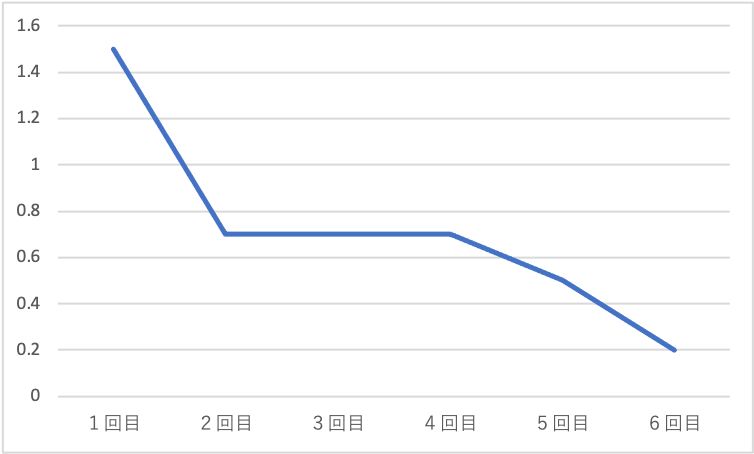

下記は治療中の疼痛の推移を示します。

体外衝撃波を6回施行し、疼痛が減少していきました。

制限なく日常生活動作をできるようになったため通院終了となりました。

縦軸 痛みの強さ 最も痛い:100 痛くない:0

横軸 施行回数